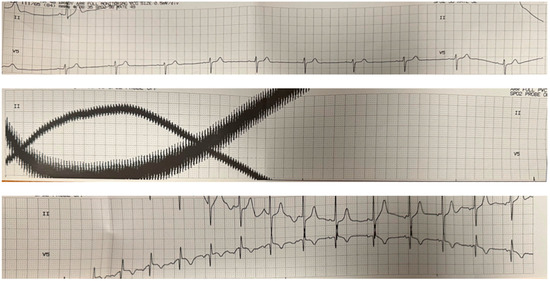

Video 1 shows the POCUS imaging of cardiac function for Patient 1 beginning before the ECT stimulus and continuing after stimulus termination. The POCUS imaging clip reveals a complete cardiac standstill for approximately 8 s during the stimulus. Figure 1 shows the EKG before, during, and after the ECT stimulus, demonstrating the electromagnetic interference corresponding to the cardiac standstill period. We observed similar findings in Patient 2 during the ECT stimulation period.

Figure 1.

EKG during ECT procedure. The top, middle, and bottom panels show continuous EKG tracings that correspond to the times prior to the ECT stimulus, during the ECT stimulus, and after the ECT stimulus, respectively. The middle panel corresponds to the time during the ECT stimulus and shows artifacts related to electromagnetic interference from the stimulus. The significant variation in the baseline signals is likely secondary to electrical interference and motion artifact.